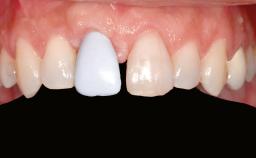

Shell Technique for Horizontal and Vertical Maxillary Bone Augmentation in a Partially Edentulous Patient with Aggressive Periodontal Disease

A 46-year-old woman was referred for treatment whose main complaints were mobility of her fixed partial dentures (right maxilla and left mandible) and periodontal bleeding during function. She also reported having taken systemic antibiotics to treat recurrent swelling in the area of the upper left molars. The patient had not seen a dentist for at least 2 years. She did not smoke and had no history of major systemic disease other than two minor orthopedic procedures some years back. The first-visit examination revealed poor plaque control, tooth mobility, periodontal disease, and a residual dentition widely associated with deep periodontal pockets.

Patient's Esthetic Expectations Low Medium High

Lip Line No exposure of papillae Exposure of papillae Full exposure of mucosa margin

Soft Tissue Anatomy Intact Defective